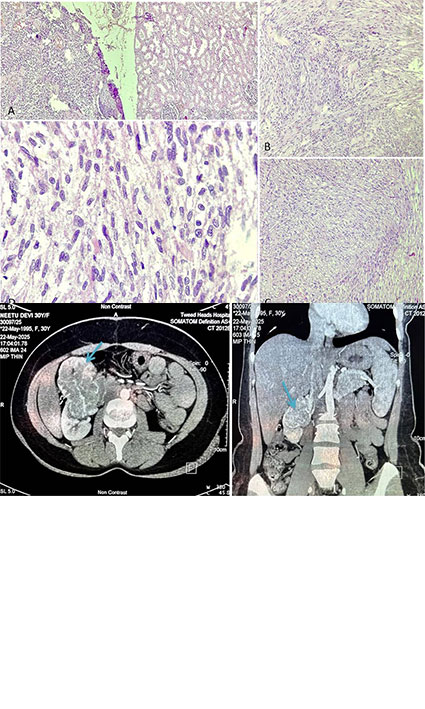

Background Primary renal leiomyosarcoma (LMS) is an exceptionally rare malignant mesenchymal tumor, constituting <1.5% of all primary renal malignanci ...

Rashi Maheshwari, Shikhar Chohan ... Sufian Zaheer

CASE REPORT | 23 Sep 2025